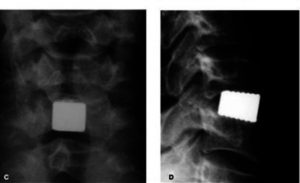

![]() |

|

Voorbeeld van Trabecular Metal cage zoals die wordt gebruikt bij de operatie via de halszijde. |

Halswervelkolom vooraanzicht en zijaanzicht, nadat er een cage is geplaatst. |